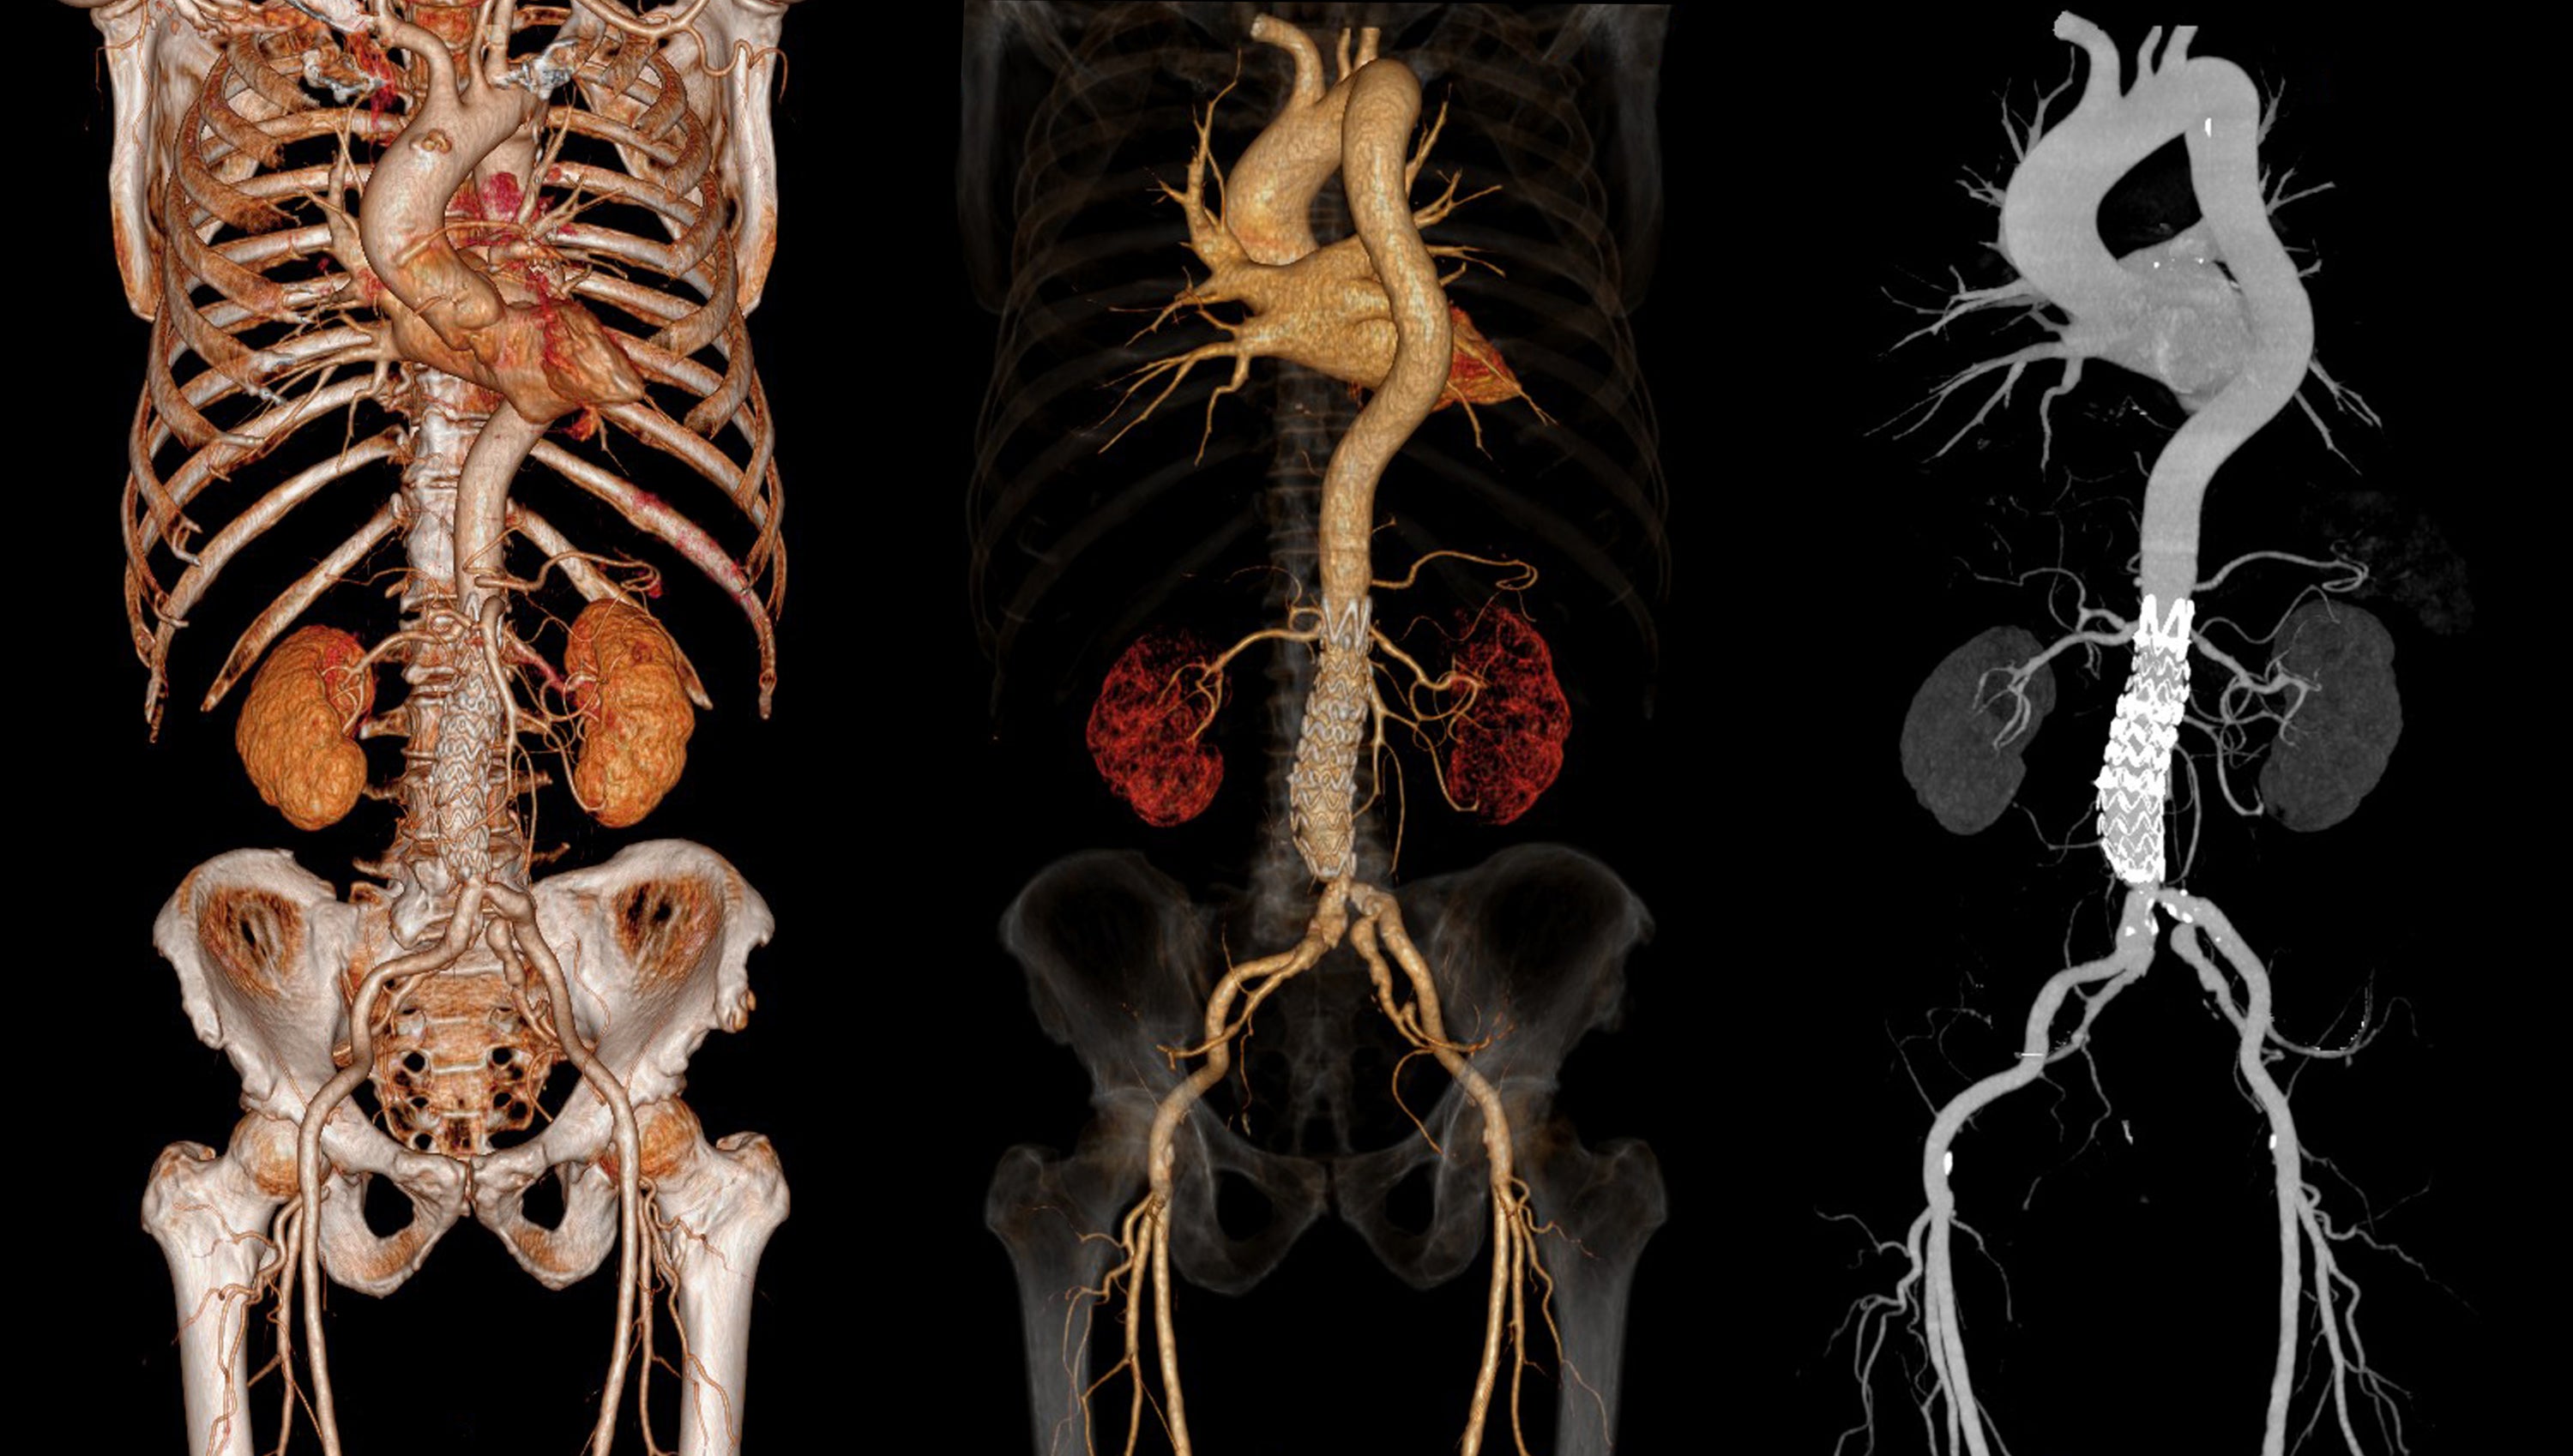

放射線診断専門医 核医学専門医 PET核医学認定医

病院で常勤医師として勤務しながら、2003年より当時黎明期であった遠隔画像診断を始める。現在は遠隔画像診断の専門医として年間1万件の診断を行っており、自社のサービス「画像診断ラウンジ」(https://radiology-lounge.com/)で遠隔画像診断を受け付けている。